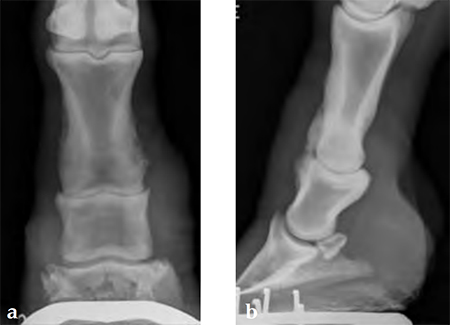

Horse with degenerative joint disease of the proximal interphalangeal joint (narrowed joint space and periosteal new bone formation).

(Case provided by Jeffrey Watkins, Tamu, USA)